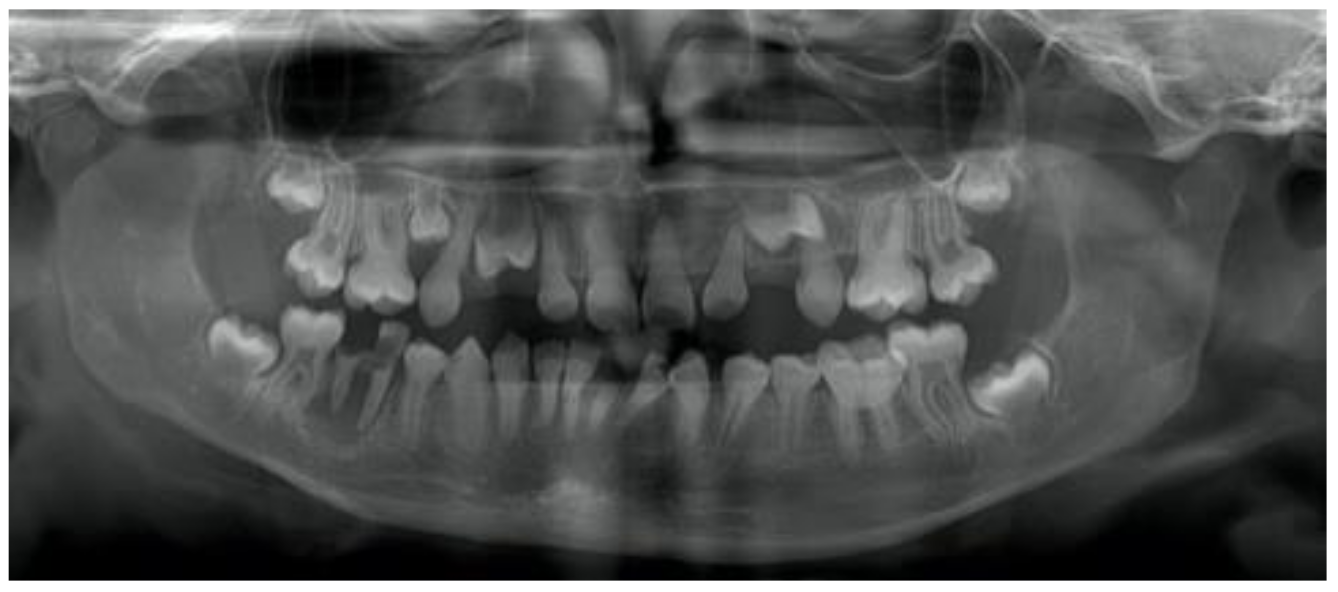

3.1. Dentinogenesis Imperfecta

3.3. Occlusion, Eruption, Impacted and Missing Teeth